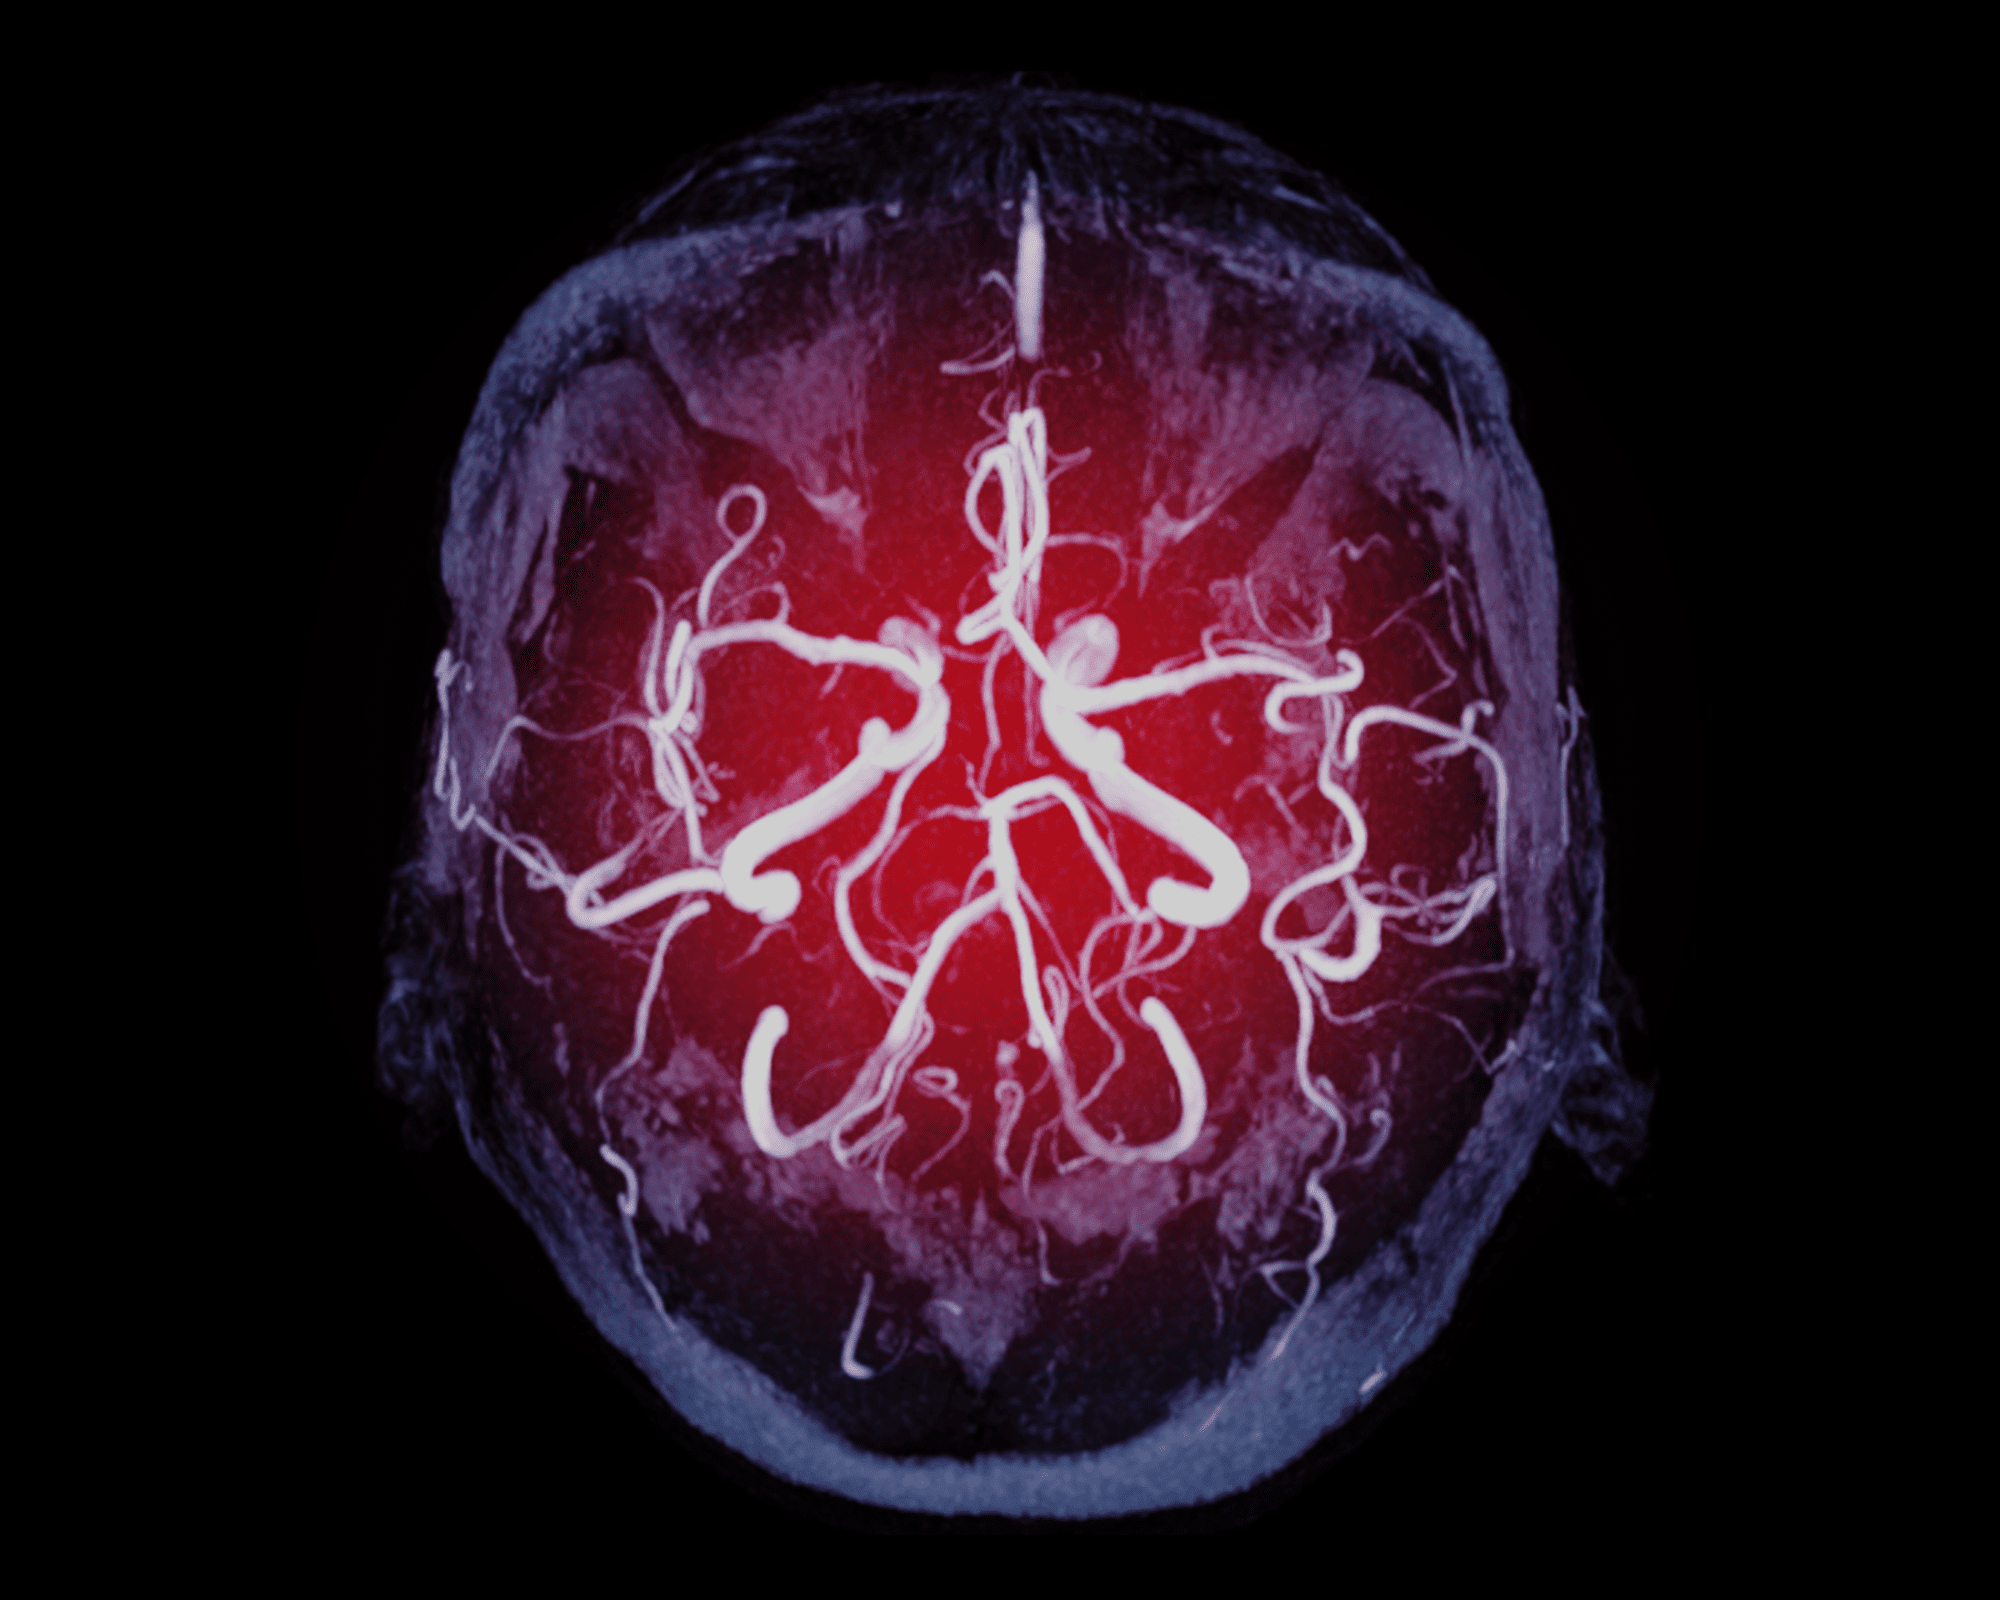

A systematic review and analysis published in the journal Interventional Neuroradiology has examined how far along “the right path” management paradigms for persistent primitive trigeminal artery (PPTA) aneurysms currently are—ultimately concluding that, while endovascular techniques in this area are successful, “meticulous” reporting of outcomes and complications remains important.

This—in addition to the fact that PPTA aneurysm treatments are “increasingly reported and commonly managed” via endovascular techniques—led Gupta et al to investigate the existing body of research further.